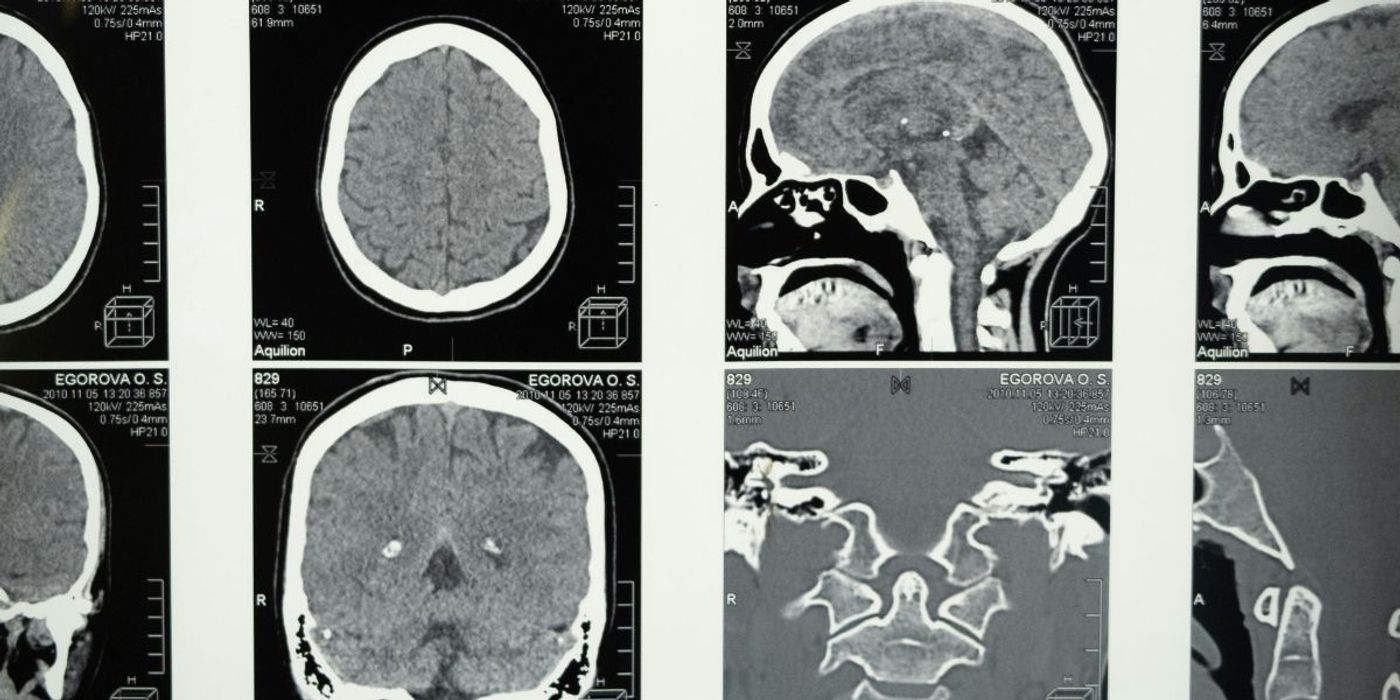

A novel nasal-delivered nanotherapy has shown promise against glioblastomas in mice. The corresponding study was published in the Proceedings of the National Academy of Sciences